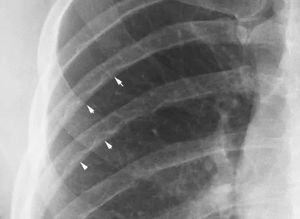

Hints-look the lower border of the ribs.

Here X ray plate showing inferior rib notching (Roesler Sign).It is seen in coarctation of aorta due to enlarge collateral vessels.Other causes include interrupted aortic arch,subclavian artery obstruction etc.